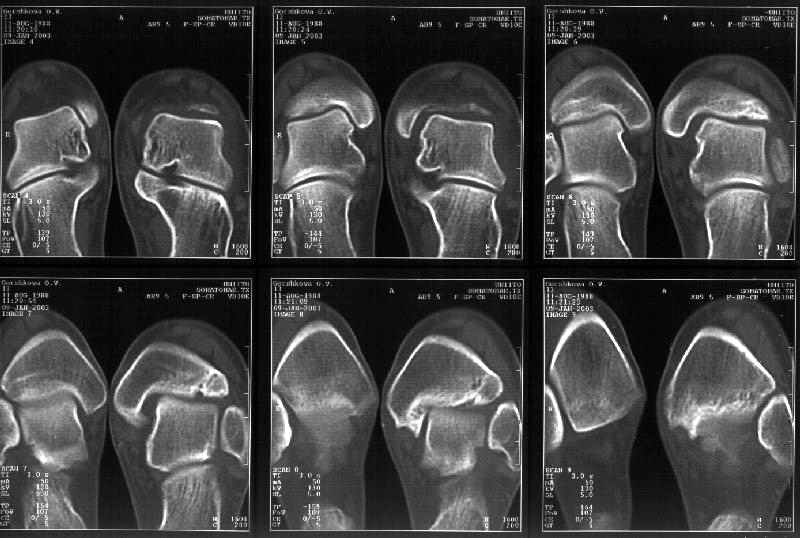

Мне в тоже время совершенно ясно видно по той же КТ, по 4 срезам, расположенным в центре и вверху пленки, что перелома внутренней лодыжки не было, в следующем собщении я приложу увеличенный фрагмент томограммы. А к этому письму прилагаю увеличеный фрагмент послеоперационной рентгенограммы, где выделил отколотый фрагмент

позади внутренней лодыжки. И он, как я вижу, находится между стержнем и тараном. А перелома внутренней лодыжки, и тем более смещения, IMHO

не определяется.

Отправитель: Alexander Chelnokov 12 Январь 2003, 14:55

> направлениях.Отдавил и отломал переднюю часть мед. маллеолюса от его

> тибиальной основы. По мне, КТ это совершенно ясно показывает.

Здесь 4 среза, начиная от основания лодыжки и проксимальнее. Где, по Вашему мнению, проходит линия перелома, отделяющая переднюю часть внутренней лодыжки от большеберцовой кости? Заранее спасибо.

Я пометил линию перелома черной линией.

К сожалению на последних присланных срезах КТ нет более низкого, через таран, среза, который был на прежнем майле. На XR я попытался показать

стержень внутри сустава и то как он раскрывает пространство между тараном и мед. малеолом.